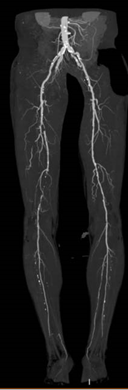

多普勒超声:右侧股浅动脉多发等至强回声斑块,中段闭塞,充满等回声。近段、远段多发充盈缺损。胫前、胫后动脉近段闭塞,胫后动脉远段由腓动脉供血。

术前CTA:右侧股浅动脉多节段重度狭窄、闭塞。

图片

术前造影:右侧股浅动脉中段重度狭窄、远端闭塞,膝下仅腓动脉通畅。

术后造影显示股浅动脉、腘动脉血流通畅,膝下造影同术前。